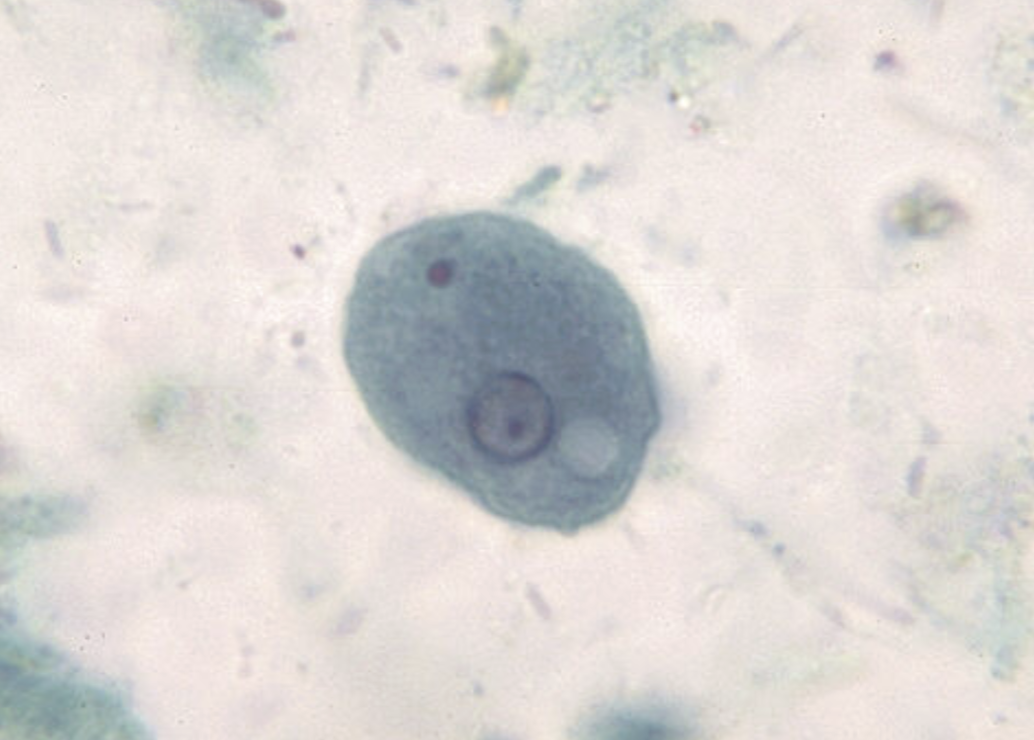

Entamoeba histolytica troph

Entamoeba histolytica troph

Chromatoid bodies have rounded or blunt ends in the Cyst form of this parasite and it is pathogenic

Entamoeba histolytica

Entamoeba histolytica cyst